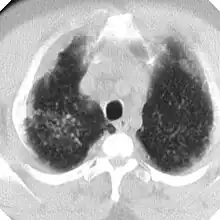

En caso de dudas diagnósticas se puede recurrir a la Tomografía Computada de Alta Resolución (TACAR) que se ha mostrado más sensible y específica para el diagnóstico.[9] Somete al paciente a mucha más radiación que la Rx y no debe usarse como prueba diagnóstica de primer nivel sino para aclarar dudas. La TACAR permite comprobar cómo las masas de FMP se originan frecuentemente en región subpleural de zonas apicales posteriores desplazándose progresivamente de la pleura —signo del desprendimiento—.[3]

La silicosis complicada se caracteriza por la presencia en los pulmones de masas de diámetro superior a 1 centímetro llamadas masas de Fibrosis Masiva Progresiva (FMP) que al retraerse generan bullas en su periferia y distorsionan los bronquios determinando obstrucción y limitación del flujo aéreo, aparte de otras complicaciones (neumotórax, cavitación aséptica, cavitación por tuberculosis, etc). Si las masas alcanzan cierto tamaño alteran notablemente los parámetros de función pulmonar, tanto de ventilación como de intercambio de gases. Silicosis aguda, la cual resulta de la exposición a cantidades muy grandes de sílice durante corto tiempo. Los pulmones se inflaman bastante y se pueden llenar de líquido, lo que causa una dificultad respiratoria grave y una baja de los niveles de oxígeno en la sangre.

La silicosis complicada se caracteriza por la existencia de masas de Fibrosis Masiva Progresiva, también llamadas masa conglomeradas, con diámetro mayor de 1 cm. Es una enfermedad grave, sobre todo si las masas son de gran tamaño, y disminuye notablemente la esperanza de vida de los pacientes. La evolución de la forma simple a complicada se debe a factores muchas veces desconocidos. Entre los factores conocidos destacan: elevada exposición a sílice, abundante profusión nodular, tuberculosis y enfermedades del colágeno.